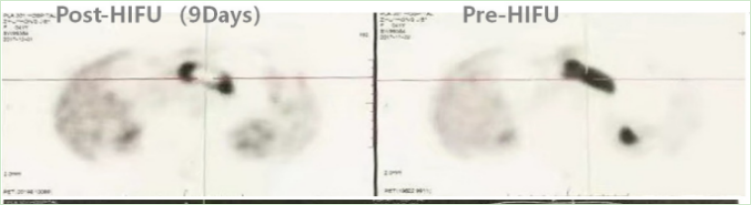

Pancreatic Cancer Treatment Case 5:

Patient: Female, 41 years old, pancreatic cancer

After 9 days of HIFU treatment, a follow-up PET-CT scan showed extensive necrosis at the center of the tumor.